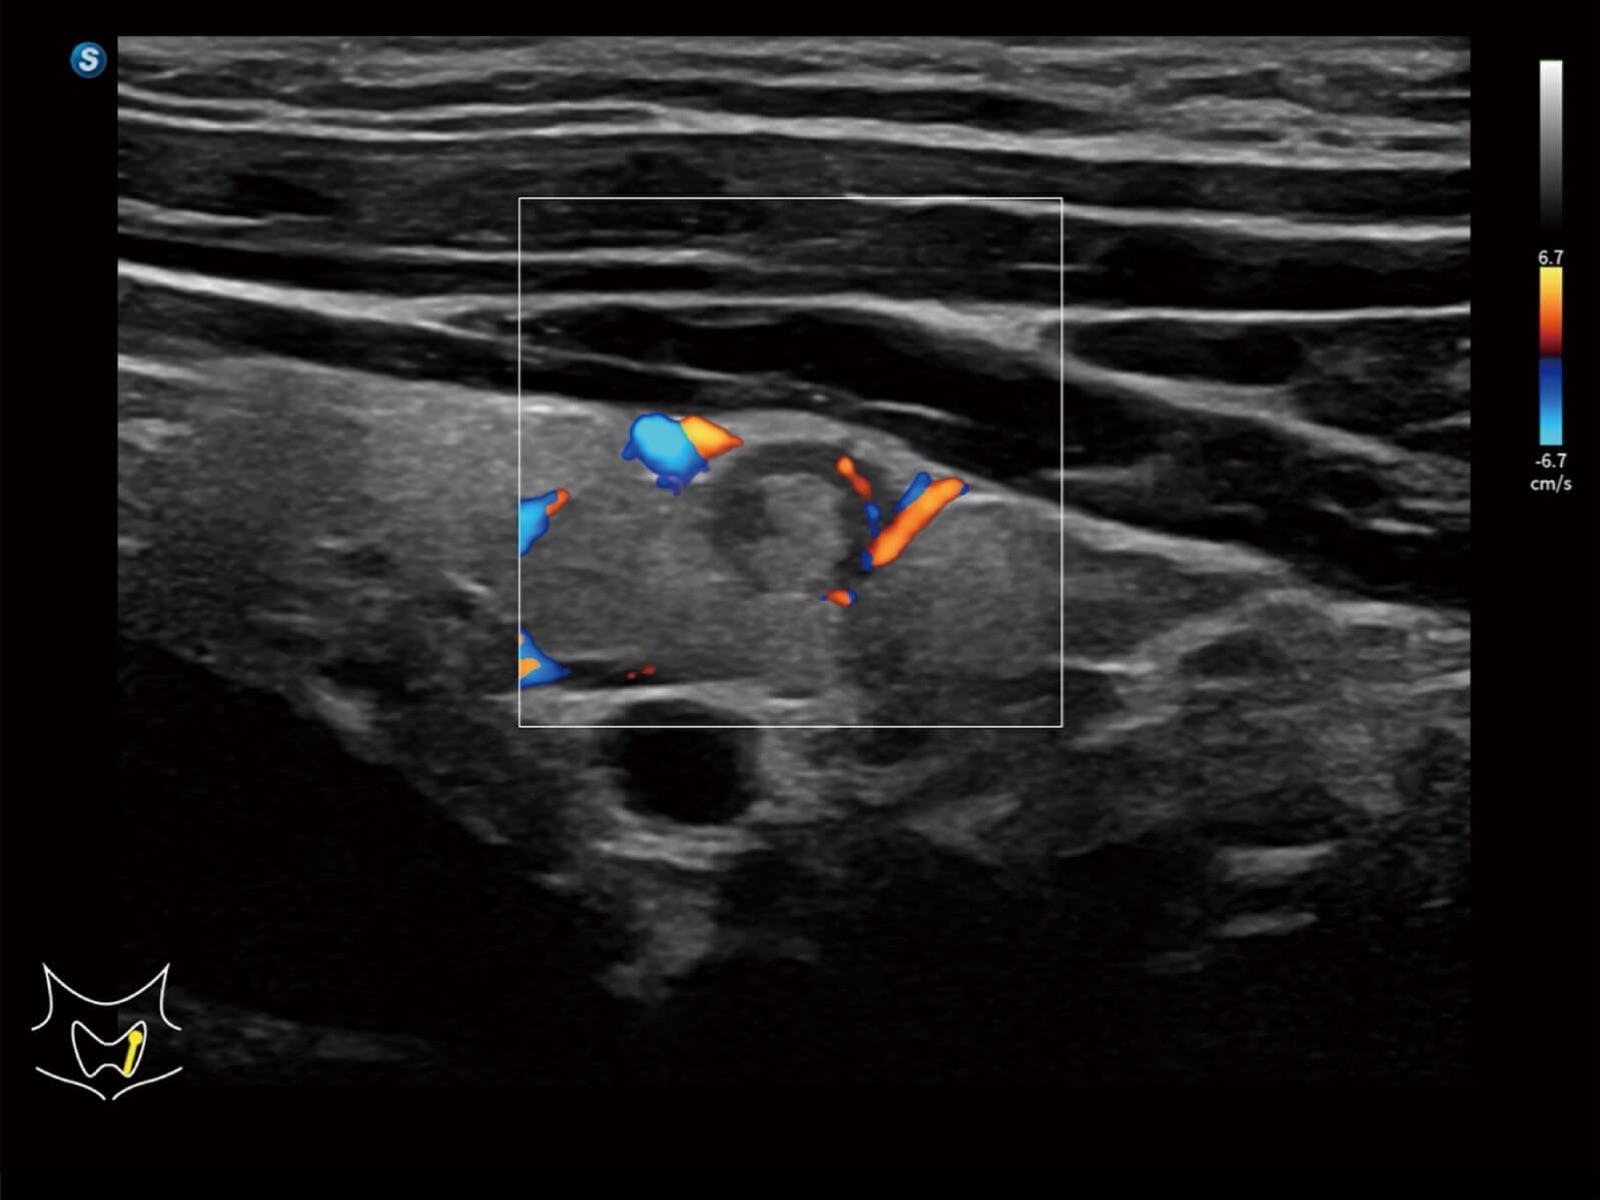

Bright Flow立体血流成像

通过光照模型,使二维血流显示出立体的效果,增加血流的敏感性、成束性,减少外溢。可以和其他不同的血流技术联合使用,轻松应对微小血管,增强血流的立体效果,提升视觉敏感性。